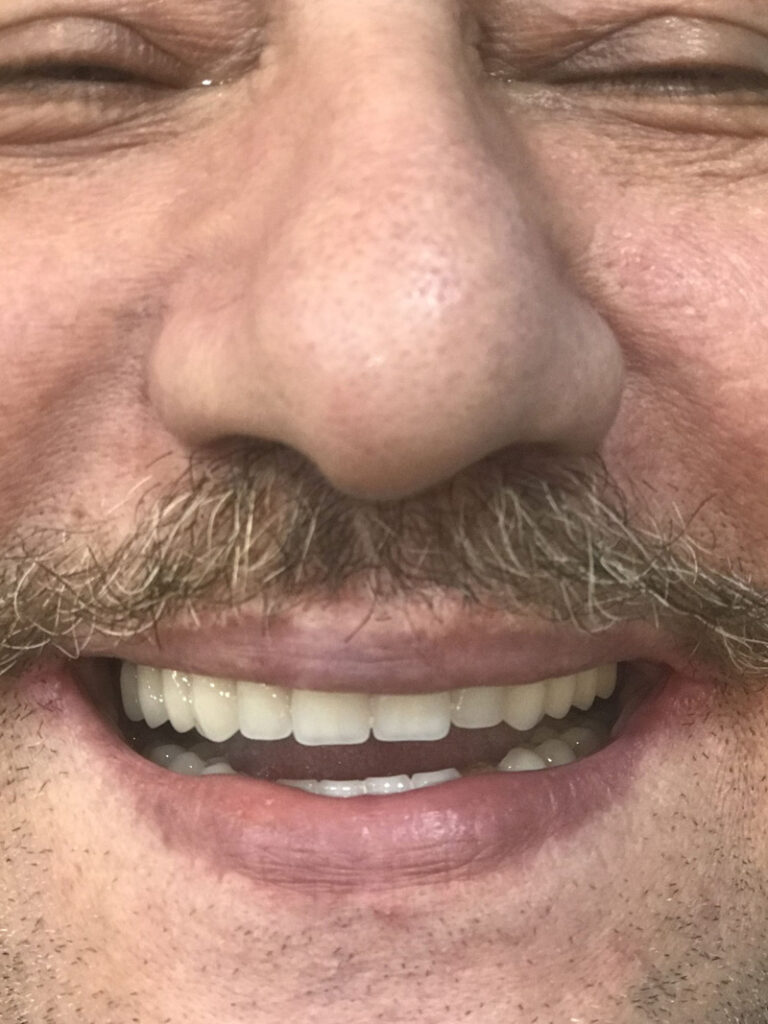

نمونه کارهای قبل و بعد از تحویل پروتز فک بالا و پایین دندان پزشکی رایان

قبل از تحویل پروتز دندان

بعد از تحویل پروتز فک بالا و پایین دندان

فیلم بعد از تحویل پروتز فک بالا و پایین دندان